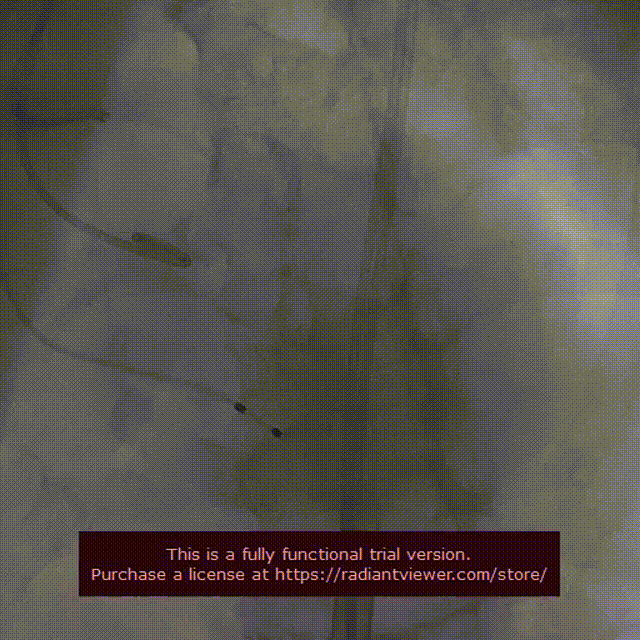

释放后造影观察存在轻微反流,测压显示压差由术前62mmhg下降至仅6mmhg。

超声显示,瓣膜工作状态正常,位置良好。

术后压差较之术前下降明显,血流动力学得到明显改善

术后彩超显示,EF值从术前的42%升高至术后的57%,患者的身体情况得到了极大的改善,取得了良好的手术效果。